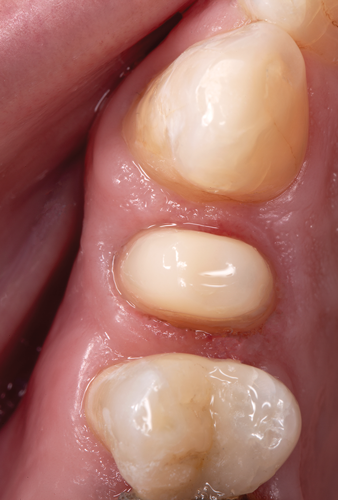

Fig 3. After endodontic treatment, crown lengthening was performed to develop an ideal ferrule effect.

Figure 3

Fig 4. An adequate collar effect of 2 mm of sound tooth structure would provide an anti-rotational feature for the stability of the crown.

Figure 4

Fig 5. Buccal view of optimal ferrule effect with a healthy biological framework.

Figure 5